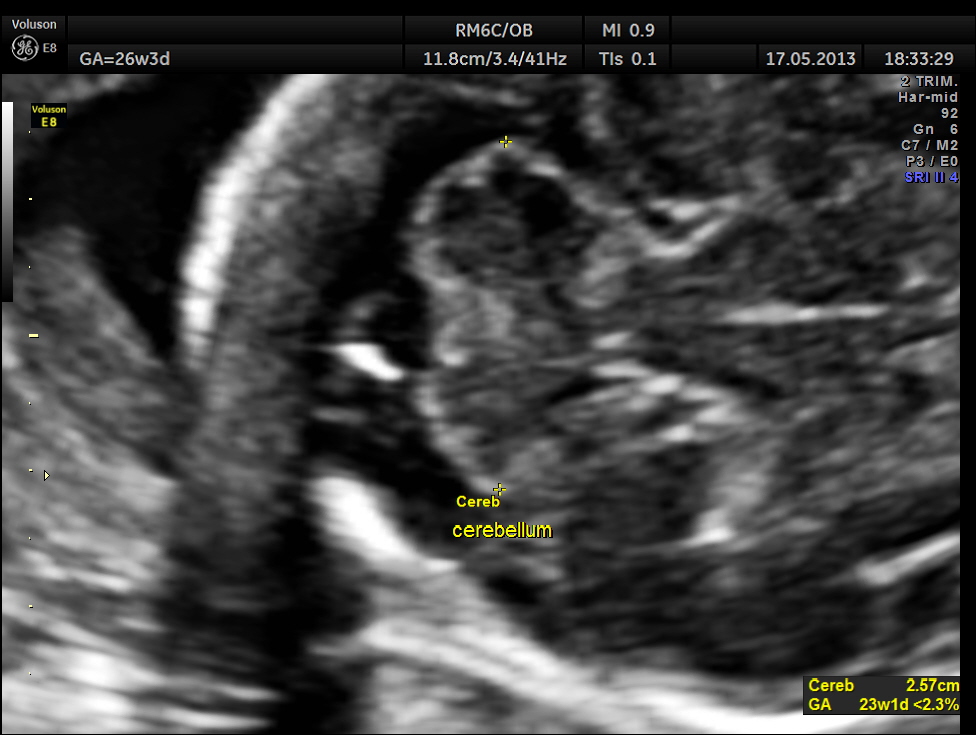

Cerebellum appears relatively smaller and corresponds to a GA of 22 to 23 weeks. Usually the cerebellum corresponds very closely to the GA and would be very useful to follow in cases of IUGR.

Cerebellum was < 2.3 %tile , suggestive of possible cerebellar hypoplasia. Unfortunately this patient was lost for follow up .